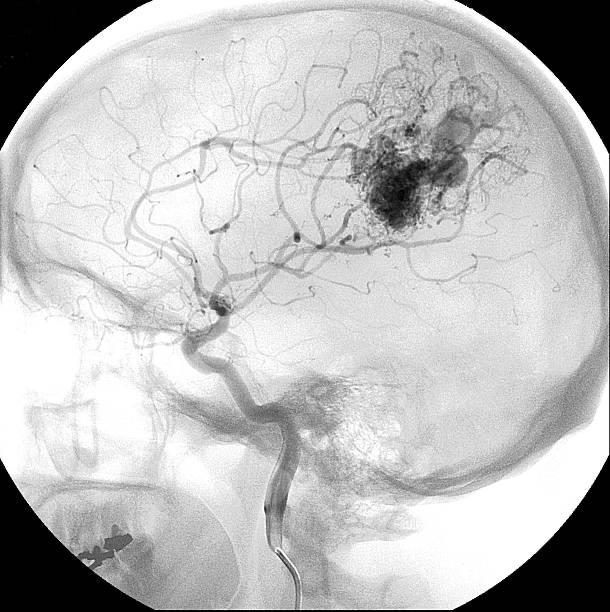

Although the dynamic and 3D three-dimensional Cerebral Digital Subtraction Angiography (DSA) is a minimally invasive examination that also involves radiation and contrast injection, it is a gold-standard final examination that is necessary for neurosurgeons before choosing a treatment plan, from arteries to microfilament vessels to venous blood vessels dynamic flow and speed, allowing doctors to fully grasp the information of brain blood vessels. In addition, DSA can help doctors in determining whether malformed blood vessels have a crisis of bursting in a short period of time, so as to determine the best medical plan and time frame for patients.

(3) Minimally Invasive Cerebral Vascular Catheter Occlusion Surgery

(Endovascular Embolization)

Depending on the clinical situation, surgical treatment for catheter occlusion can be performed independently, before microscopic surgical resection, or before radiation therapy to reduce the volume and extent of cerebral arteriovenous malformations. The neurosurgeon will use a very fine catheter from the artery in the groin of the patient’s thigh through the large artery in the patient’s body, travel the catheter to the blood vessels of the patient’s brain under X-ray navigation, and then inject very fine titanium wire, plastic bead balls or special glue into the blood vessels of the arteriovenous malformation to embolize the arteries that supply the malformed blood vessels and the center of the malformed blood vessels. The main risk of this surgery is that normal and malformed blood vessels are accidentally injured during the operation, causing them to become blocked or rupture and bleed, resulting in ischemic or hemorrhagic stroke. Another risk of surgery is that during the process, the venous blood vessels responsible for draining the blood from the malformed blood vessels are accidentally blocked prematurely, so that the blood in the malformed blood vessels is discharged, and the blood pressure rises rapidly, resulting in the explosion of hemangiomas.